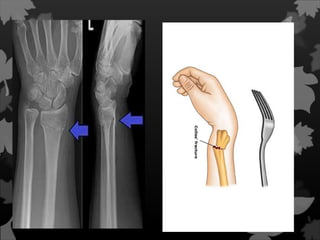

Fraturas de Smithe Colles Fratura que acomete a parte distal do rádio.

Fratura de Monteggia Éuma fratura da ulna que afeta a articulação com o rádio. Mais precisamente, é uma fratura do terço proximal da ulna com deslocamento da cabeça do rádio.

Fratura de Galeazzi Umafratura de Galeazzi é uma fratura da região distal do rádio com ruptura da membrana interóssea e da ligação com a ulna, com subluxação da ulna.